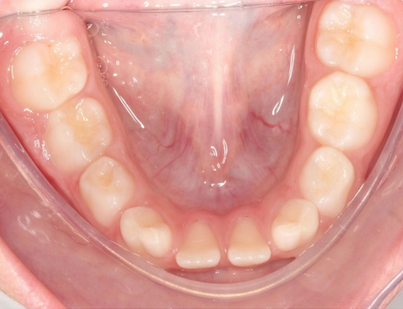

Na imagem abaixo é possível ver a foto oclusal inferior de uma menina de 6 anos de idade com fusão dos dentes 72 e 73, 82 e 83 e agenesia dos dentes 32 e 42.